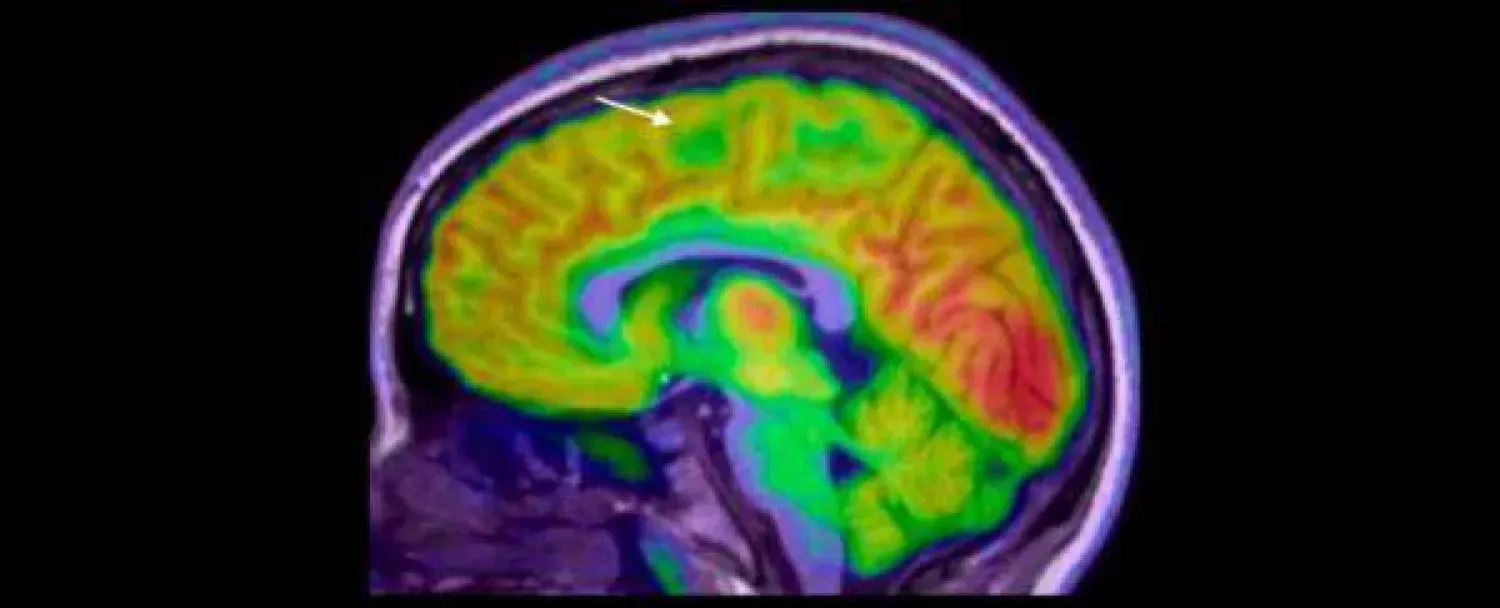

نجح فريق بحثي من «معهد مردوخ لبحوث الأطفال» (Murdoch Children's Research)، والمستشفى الملكي للأطفال، بملبورن في أستراليا، في تطوير جهاز لتشخيص الصرع بالذكاء، يستطيع رصد وجود خلل في أنسجة القشرة المخية، لا يمكن رصده من خلال فحص الأشعة العادي.

وأوضحت الدراسة التي نُشرت في نهاية شهر سبتمبر من العام الحالي، في مجلة «الصرع» (Epilepsia)، أن الجهاز الجديد قادر على التشخيص بدقة لأي خلل صغير في أنسجة القشرة المخية، ما يؤدي إلى تدخلات جراحية أسرع لعلاج حالات الصرع العنيفة، ومن ثَمَّ تقليل تكرار النوبات، وتحسين نتائج النمو على المدى الطويل.

قام الباحثون باستخدام التصوير بالرنين المغناطيسي لتدريب الجهاز الجديد، وبعد ذلك قاموا بتقسيم الأطفال إلى مجموعتين للتدريب، كما استُخدمت مجموعة منفصلة من فحوصات البالغين للتحقق الإضافي من أداء الجهاز.

أكد الباحثون أن اكتشاف وجود الخلل في نسيج القشرة المخية من خلال فحوصات الرنين المغناطيسي الروتينية، يُعد أمراً بالغ الصعوبة؛ حيث يتم التعرف على أقل من نصفها فقط في أول فحص للطفل، ما يؤخر التشخيص، ومن ثَمَّ يحرم الطفل من فرصة إجراء الجراحة في وقت مبكر، وكلما طالت مدة معاناة الطفل من النوبات شديدة الحدة، زاد احتمال إصابته بصعوبات التعلم، بما في ذلك الإعاقة الذهنية.